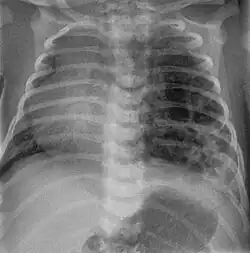

Congenital pulmonary airway malformation

Congenital pulmonary airway malformation (CPAM) is a rare disease in which the lung airways develop abnormally in the fetus. This leads to infants having pockets of air and cystic masses in their lungs. These can expand in size and cause a mediastinal shift, especially in the higher grades of CPAM. Diagnosis is usually made on ultrasound and supplemented with x-ray, CT, or MRI to further define the malformation. On chest x-ray, CPAM has varying appearances but may look like "bubbles" within the lung fields.[26]